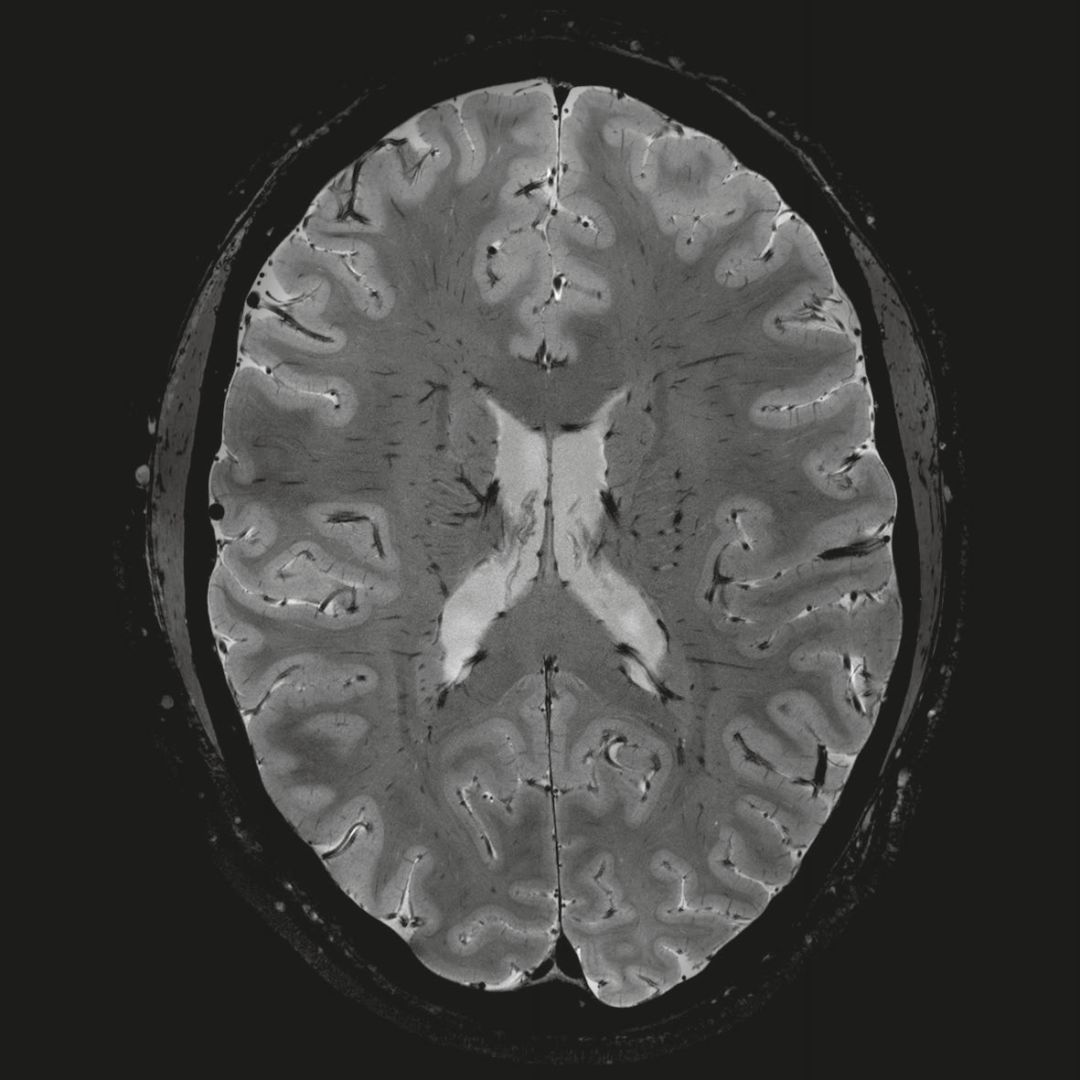

1毫米的各向同性分辨率DTI:神經(jīng)纖維束的交叉細節(jié)顯示

0.8毫米的各向同性分辨率:精確劃分灰質(zhì)和白質(zhì)

0.8毫米的各向同性分辨率:超精細的解剖細節(jié),例:小腦的精細結(jié)構(gòu)

超精細的解剖細節(jié):T2對比

0.17 x 0.17 x 0.8毫米分辨率超高。